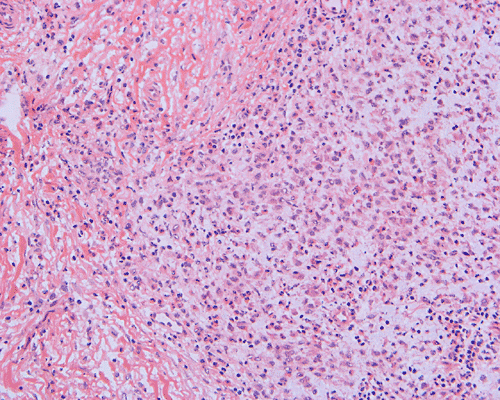

Clinical information: The patient was a 13 year-old girl who presented with worsening headache and some difficulties with memory, concentration and attention. MRI studies disclosed a 2.1 x 1.9 x 1.8 cm enhancing mass in the left temporal bone and sphenoid wing. The mass extended intracranially and abuts the left temporal bone accompanied by dural enhancement at that location. There is also extension through the bone into the submuscular temporal region. The following photos are taken from representative regions of the lesion. Panel 1 and 2 are CT scans at soft tissue and bone density respectively. Panel 3 and 4 are T1 weighed images without and with contrast respectively. Pandl 5 is proton density image. Panel A to D are cytologic (squash) prepartion for intra-operative consultation. Panel E and F are frozen sections for intraoperative consultation. Panel G to L are paraffin embedded sections.

Morphologic features are often sufficient to make an accurate diagnosis. Typical lesions are composed of medium sized to large Langerhans’ cells mixed with non-neopalstic inflammatory cells. The amount of eosinophils can vary from none 3 or scant to substantial. The Langerhans’ cells have only slight degree of atypia. Many of the nuclei have a characteristic deep groove parallel to the long axis, the so-called “coffee bean” nuclei. The amount of cytoplasm is usually moderate. Histiocytes (macrophages) are usually present and can be multinucleated. When histiocytes are present in large amount, they may make the diagnosis difficult. Similar to their non-neoplastic counterparts, tumor cells in Langerhans’ cell histiocytosis are positive for CD1a and S100 by immunohistochemistry. Histiocytes, on the other hands, are negative for S100 and CD1a 4, 5, 6 CD68 is helpful but not entirely specific in separating histiocytes from tumor cells in Langerhans’ cell histiocytosis. The proliferating fraction of can be recognized by immunohistochemistry for Ki67 (MIB-1) 6.